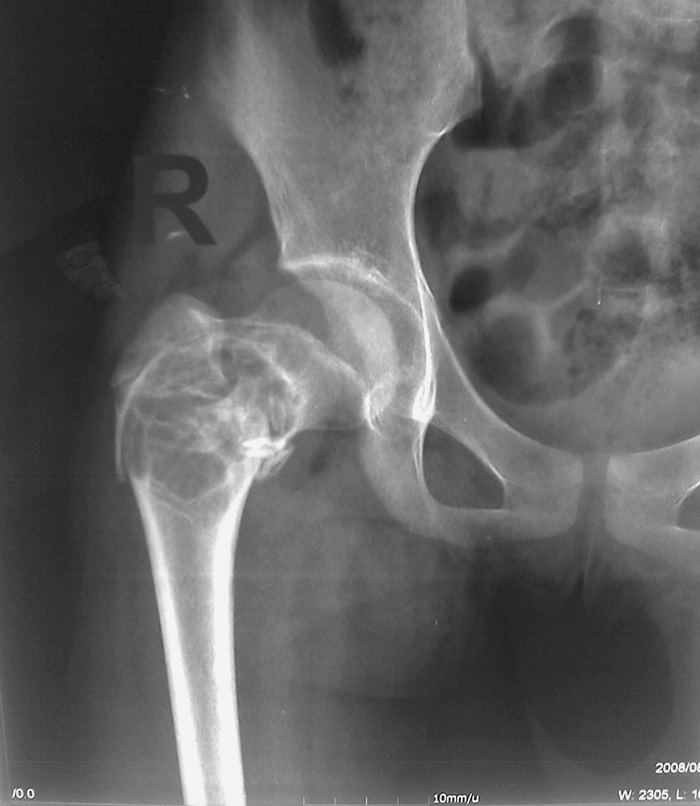

以下是引用zxd95在2008-8-18 17:49:00的发言:[br]右股骨粗隆间囊性病变(骨囊肿?动脉瘤样骨囊肿?)伴病理性骨折。

以下是引用前行在2008-8-18 18:14:00的发言:[br]粗隆间骨囊肿并病理性骨折。

以下是引用随光逐影在2008-8-18 19:54:00的发言:[br]考虑右股骨粗隆间良性骨肿瘤或骨肿瘤样病变(骨囊肿?)并病理性骨折。